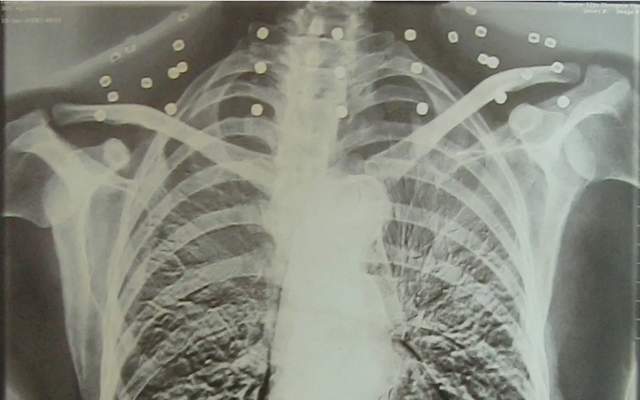

CT影像里所谓的“项链”

原来是炸弹爆炸后

散出的33枚钢珠

吴以先指着CT胶片上的白点

讲述着60年前

那场惊心动魄的战斗

那些嵌入颈部的弹珠

仅差几毫米就会击穿他的颈部动脉

弹珠一直留在吴以先体内

“这些弹珠在我身体中这么久了

医生说不会影响我的生活

只是在气温变化时有痛感”